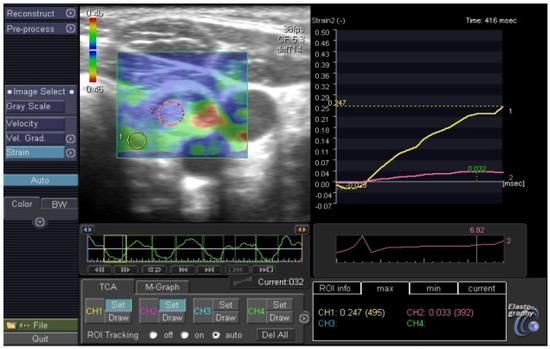

- Dietrich, C.F.; Barr, R.G.; Farrokh, A.; Dighe, M.; Hocke, M.; Jenssen, C.; Dong, Y.; Saftoiu, A.; Havre, R.F. Strain Elastography—How to do it? Ultrasound Int. Open 2017, 3, E137–E149. [Google Scholar] [CrossRef] [PubMed]

- Monpeyssen, H.; Tramalloni, J.; Poirée, S.; Hélénon, O.; Correas, J.M. Elastography of the thyroid. Diagn. Interv. Imaging 2013, 94, 535–544. [Google Scholar] [CrossRef] [PubMed][Green Version]

- Carneiro-Pla, D. Ultrasound Elastography in the evaluation of thyroid nodules for thyroid cancer. Curr. Opin. Oncol. 2013, 25, 1–5. [Google Scholar] [CrossRef] [PubMed]

- Borysewicz-Sanczyk, H.; Dzieciol, J.; Sawicka, B.; Bossowski, A. Practical Application of Elastography in the Diagnosis of Thyroid Nodules in Children and Adolescents. Horm. Res. Paediatr. 2016, 86, 39–44. [Google Scholar] [CrossRef]

- Cunha, G.B.; Marino, L.C.I.; Yamaya, A.; Kochi, C.; Monte, O.; Longui, C.A.; Cury, A.N.; Fleury, E.D. Elastography for the evaluation of thyroid nodules in pediatric patients. Radiol. Bras. 2019, 52, 141–147. [Google Scholar] [CrossRef]